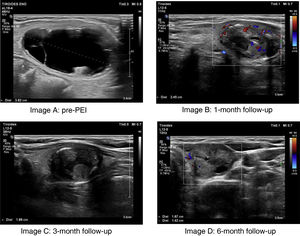

After the procedure, the patient was monitored by the day hospital endocrinology nursing staff for 45 minutes. Oxygen saturation and possible immediate complications (pain and/or local hematoma) were monitored. If clinically stable, the patient was discharged with clinical and ultrasound follow-up scheduled at 1, 3, and 6 months. Fig. 2 shows the evolution of a cystic thyroid nodule subjected to PEI.

Initial and final ultrasound images of a thyroid nodule treated with percutaneous ethanol injection and ethanol aspiration. A) Pre-PEI cystic thyroid nodule with a maximum diameter of 3.8 cm (nodule volume, 17.10 mL). B) Color Doppler mode ultrasound image at the 1-month follow-up showing minimal peripheral Doppler uptake and a reduction in nodule size with a maximum diameter of 2.4 cm (nodule volume, 2.69 mL, VRR, 84.28%). C) Ultrasound image at the 3-month follow-up showing a reduction in nodule size with a maximum diameter of 1.89 cm (nodule volume, 1.72 mL, VRR, 89.94%). D) Color Doppler mode ultrasound image at the 6-month follolw-up showing persistent minimal peripheral Doppler uptake and almost complete disappearance of the cystic component (final nodule volume, 1.64 mL, VRR, 90.42%).